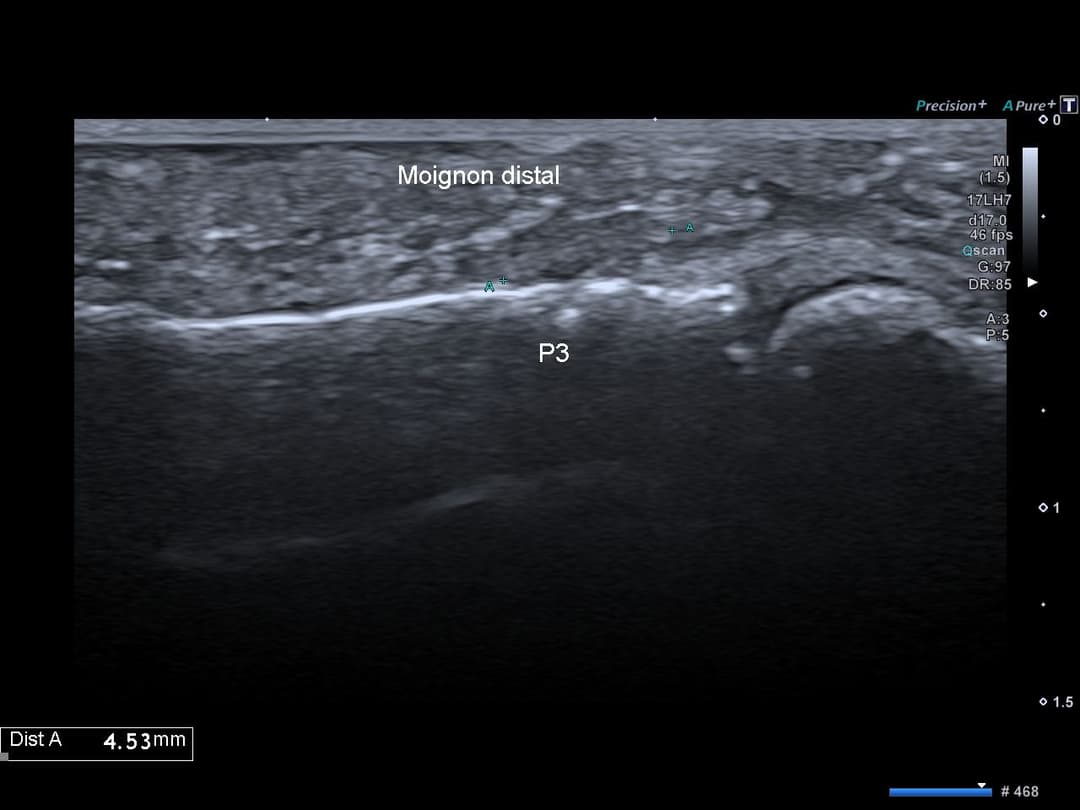

Échographie

Rupture complète du tendon fléchisseur profond avec persistance d'un petit moignon tendineux à son enthèse sur la 3ème phalange.